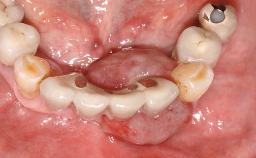

Surgical treatment of a 67-year-old male patient exhibiting an extended edentulous space in the anterior maxilla after the removal of three hopeless incisor teeth.

The video demonstrates implant placement using a surgical stent according to the principle of prosthodontically driven implant placement. The deficient ridge is augmented with locally harvested autologous bone chips, a superficial layer of xenogenic DBBM particles and a resorbable collagen membrane. The surgery is completed with a precise, tension-free primary wound closure.

Bone Augmentation Horizontal|Simultaneous

Augmentation Materials Autogenous chips|Xenogenous|Membrane